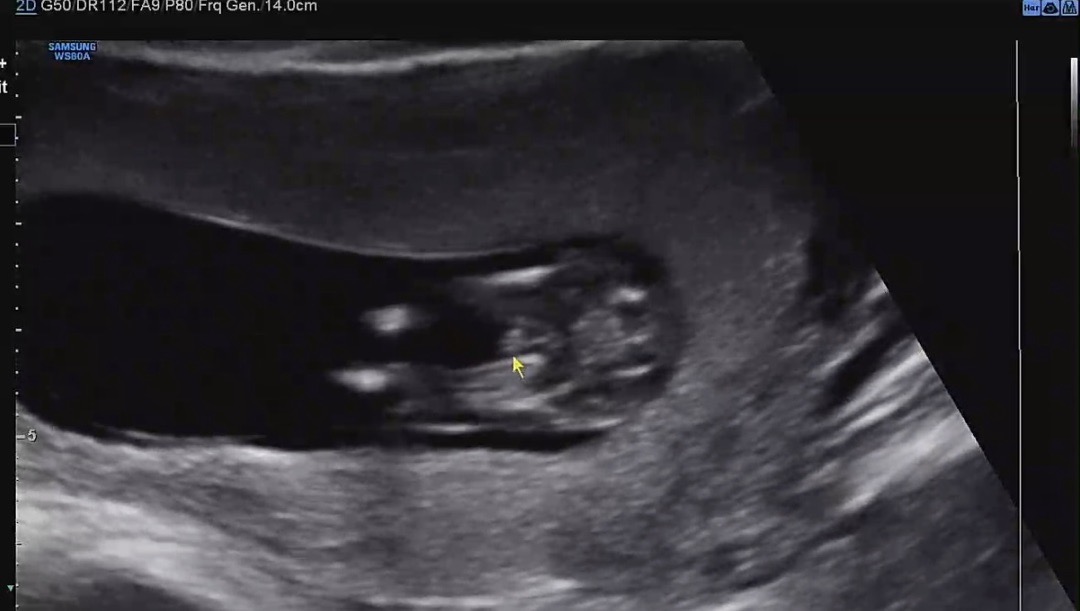

12주 5일차 고수님들 성별 봐주세요..🤍

어때보이시나요?!? 의사선생님은 다리 사이에 뭐가 보이는데 1~2주 더 지나야 알 수 있을 거 같다하셨어요🥹 저렇게 보이는 건 아들인가요?